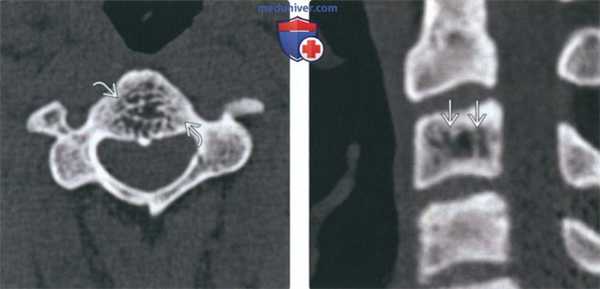

(Слева) На аксиальной КТ без КУ визуализируется относительно хорошо отграниченный участок без склеротического ободка. Ключевые диагностические признаки: «жировая» плотность и картина «пчелиных сот».

(Справа) На сагиттальной реформатированной КТ определяется гиподенсный участок в теле СЗ с немногочисленными утолщенными трабекулами, ориентированными вертикально (характерные КТ-признаки гемангиомы позвонка). Вертикальные трабекулы не всегда соединяют обе замы кегельные пластинки.

(Слева) На аксиальной МРТ (Т2 ВИ) отчетливо определяются ожидаемые признаки гемангиомы позвонка. В изоинтенсивном объемном образовании ограниченным телом позвонка, визуализируются трабекулы и жировая ткань.

(Справа) На сагиттальной MPT (STIR) определяется полное подавление сигнала в типичной гемангиоме, целиком представленной жировой тканью. Картина гемангиомы на Т2 ВИ вариабельна и зависит от жировых и сосудистых элементов.